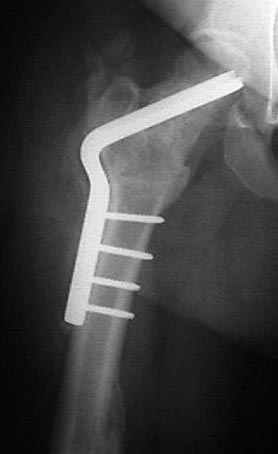

Отправитель: Alexander Chelnokov 23 Ноябрь 2004, 02:31

Если, например, доводится лечить больных с псевдартрозами шейки бедра, то надобность есть, и приходится. См. приложение.

Несколько снимков из моей коллекции, чтобы разьяснить, почему мы до сих пор делаем различные варианты остеотомии.

На рисунке N1 предоперационный план лечения ложного сустава шейки бедра- линия ложного сустава, угол и направление введения импланта, клиновидная остеотомия в градусах и миллиметрах, второй снимок после коррекции, расчет, на сколько удлиняется конечность и размеры импланта;

N3 рисунок окончательный снимок, после операции моя рентгенограмма должен выглядеть примерно как эта картина. На N4 снимке клин перед удалением; N5 послеоперации 3 нед.; N6 окончательная рентгенограмма.

(доложен в Ст. Петербурге 2003 и в Москве 2004)

варус при проксимальном отделе 95 градусной пластиной.